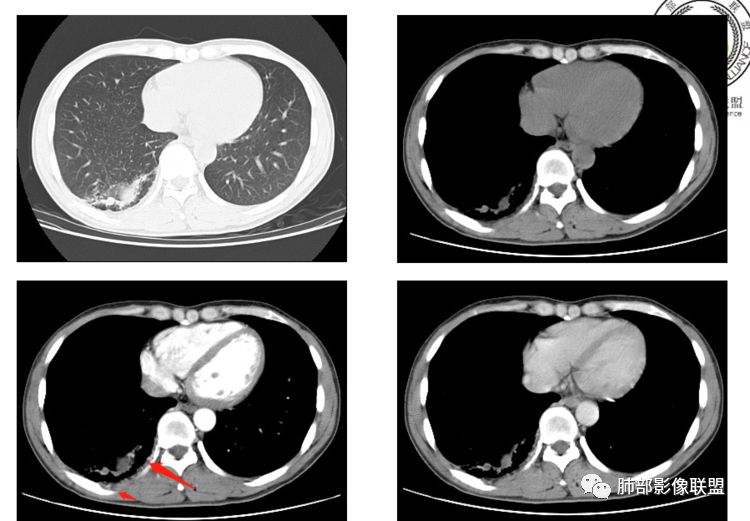

第一,看支气管,有一条支气管从病变边缘走过,有一条支气管在病灶近端堵塞;说明病变和支气管有关系,一般情况下支气管堵塞应该考虑炎性病变或恶性肿瘤才可以符合,不符合良性肿瘤,当然肺囊肿也可以,因为它是先天发育变异的。

第二,看强化幅度,内无强化,但是我担心图像并不够薄,目测观察有所偏差,但是现可见薄壁样强化;从这个角度考虑,良性肿瘤就不符合了,如PSP就不太支持了,这个病变远端有分叶、有小尾巴,周围有索条状影,除非PSP合并感染,二元论,否则单纯PSP周围不会有这种表现。

第三,病变旁边胸膜区域有增厚,似乎有些血管增粗,虽然这不是隔离征好发区域;它应该偏内侧一点,但是我们应该最好有重建血管先排除隔离征;从所给图片看,病灶具体走形外面没有看见血管进入,因为是囊性病变嘛。

第四,病变为薄壁环状强化,就两种可能,

1 是病变内为囊性成分,即囊肿,周围病变考虑合并感染;      2 是病变内是干酪坏死,周围是薄壁强化,然后是一点纤维组织,再周围是一些结核的病灶;

但是有些疑惑:

首先周围病变肯定是感染性病变;索条状的,但是囊肿伴这样感染,真的很少见;

其次病变周围有索条、肺气肿,这些慢性病的改变;还有就是形态,似乎是稍长点的形态;这几点就更符合结核的表现,但是周围病灶没有树芽征,都是索条;结核这样子的干酪样坏死,也少见,壁薄呈这样,就一层纤维;附近的血管又这么粗;

但是我们先把方向锁定在炎性病变;囊肿伴感染还是结核,这两个在图片上各自特点都有,从目前条件无法完全典型的分辨出来;但是还是倾向于囊肿合并感染。